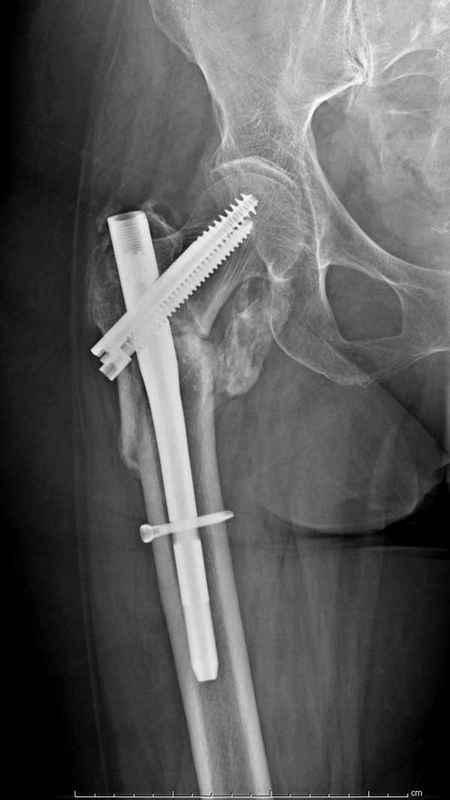

Из фиксаторов, мы бы применили цефаломедуллярные, потому что они "по закону моментов" из-за короткого рычага от центра головки к диафизу и по принципу "головка диафиз" механически лучше выдерживают нагрузки, чем пластины.

Но современные пластины с угловой стабильностью не отстают от медуллярных конструкций. Межфрагментарные шурупы и имплант как нейтрализирующее создаст адекватную фиксацию.

Здесь 83 года, травма в результате падения